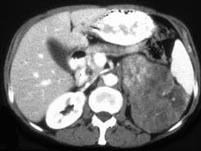

问题 女,43岁,满月脸、皮肤紫纹、月经不规则3个月余,请结合所提供图像,作出诊断 ( )

选项 A、左肾上腺腺癌 B、左肾上腺增生 C、左肾上腺嗜铬细胞瘤 D、左肾上腺转移瘤 E、左肾上腺腺瘤

答案 A